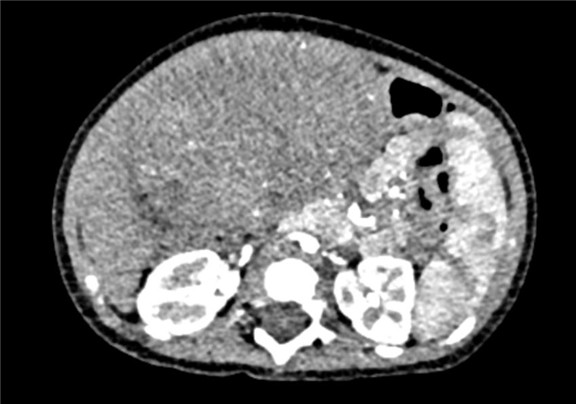

术前CT检查:

动脉期

静脉期

将0.625mm双源薄层CT资料的静脉期和动脉期Dicom格式文件导入海信CAS系统。

通过调节窗宽窗位调整CT序号,对肝实质,胆囊,下腔静脉,肿瘤,肝动脉、门静脉及肝静脉等进行三维重建;系统自动计算肝脏体积。

模拟手术操作,自动计算切除肿瘤体积。肝脏体积为310.9ml,肿瘤体积为437.7ml,肿瘤体积是肝体积的1.4倍,通过比对9-12月正常肝脏体积为321.13±118.91ml,通过术前模拟手术,精准判断切除后剩余肝脏体积能耐受,避免肝衰竭发生。